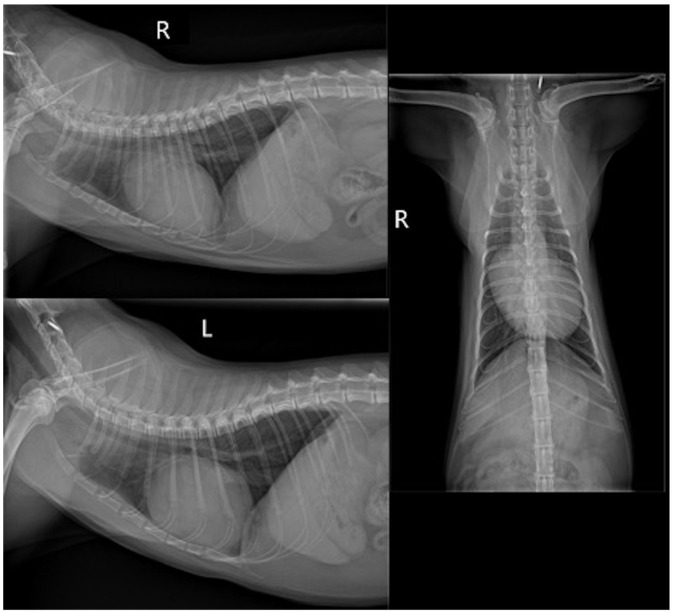

病例摘要:本报告描述了一只患有肺发育疾病和肺动脉高压高风险的幼猫的候选基因叉头盒 F1 (FOXF1) 的诊断结果、自然病史和遗传分析。一只 1 岁大的雄性全Chartreux猫因心脏杂音调查和运动不耐受而被转诊。超声心动图检查发现三尖瓣反流射流速度较快,并伴有右侧心脏变化,肺动脉高压的可能性很高。没有发现先天性心脏分流或左侧心脏病变,支持肺动脉高压的原发性心脏病因。对患者进行了广泛的实验室检查、胸部X光检查和CT检查。组织病理学鉴定(肺活检和随后的尸检)是最终诊断的必要条件。确诊八个月后,该猫出现右侧充血性心力衰竭,最终导致安乐死。从确诊到死亡的存活期为 12 个月:发育性肺病属于人类弥漫性肺病的一种,与肺动脉高压有关。描述猫肺发育障碍的兽医文献很少,本报告提供了有关临床表现和病情发展的信息以及全面的诊断工作,这可能有助于临床医生识别这种疾病。肺部活检是最终诊断的关键。未发现 FOXF1 的致病变异。

Case summary: This report describes the diagnostic findings, natural history and genetic analysis of the candidate gene Forkhead Box F1 (FOXF1) in a young cat with developmental lung disease and high probability of pulmonary hypertension. A 1-year-old male entire Chartreux cat was referred for cardiac murmur investigation and exercise intolerance. Echocardiography identified a high-velocity tricuspid regurgitant jet with right-sided cardiac changes, supporting a high probability of pulmonary hypertension. No congenital cardiac shunts or left-sided cardiac changes were found to support a primary cardiac cause of pulmonary hypertension. Extensive laboratory work, thoracic radiographs and CT were performed. Histopathological characterisation (lung biopsy and later post mortem) was necessary to reach the final diagnosis. Eight months after diagnosis, the cat developed right-sided congestive heart failure, eventually leading to euthanasia. Survival from diagnosis to death was 12 months.